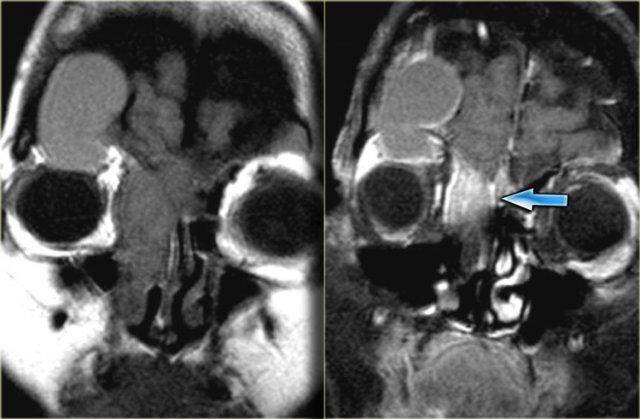

Bên trái là chuỗi xung T1W mặt phẳng axial, bên phải là chuỗi xung T2W mặt phẳng coronal.

Có bất thường ở bên trái, nhưng ở mức độ ít hơn cũng có ở bên phải.

Hãy cố gắng xác định các cấu trúc nào bị tổn thương.

Các mũi tên vàng chỉ vào ống lệ mũi.

Túi lệ kết nối với ống lệ, sau đó dẫn lưu vào ngách mũi dưới.

Bên trái có phù nề mô mềm quanh hốc mắt trước vách ngăn.

Trên hình ảnh coronal, có tín hiệu cao hai bên tại vị trí nối giữa ống lệ mũi và túi lệ, gợi ý ổ dịch.

Bên trái cũng có phù nề mô xung quanh.

Chuỗi xung T1W sau tiêm thuốc tương phản từ, mặt phẳng axial và coronal.

Ở phía ngoài ống lệ mũi hai bên, có các ổ dịch hiện nay cho thấy hình ảnh ngấm thuốc ngoại vi.

Các hình ảnh bổ sung (chuỗi xung T2W) cho thấy bệnh lý niêm mạc xoang hàm phải và mức dịch trong xoang hàm trái, ngoài ra còn có bệnh lý xoang sàng và xoang bướm lan rộng.

Bệnh nhân này bị viêm xoang cấp tính có biến chứng viêm mô tế bào hốc mắt và viêm túi lệ kèm áp xe.

Hẹp ống lệ mũi do bẩm sinh hoặc do viêm là yếu tố nguy cơ dẫn đến viêm túi lệ.